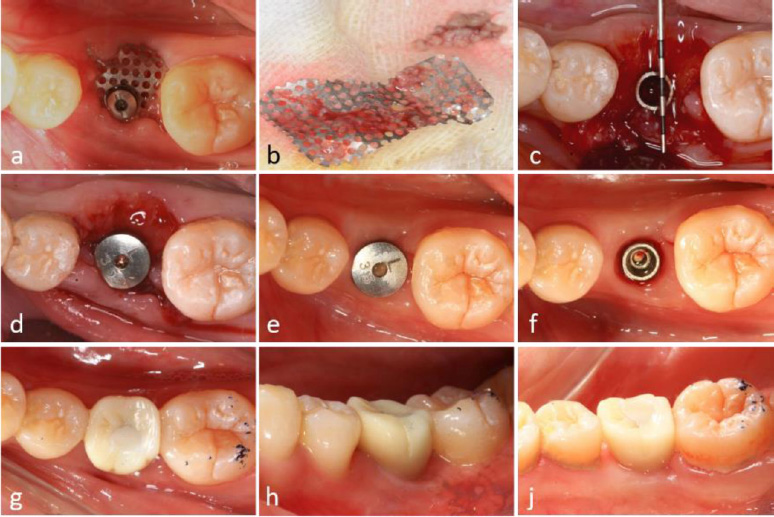

A modified healing abutment was developed to secure a prefabricated titanium mesh on top of the dental implant, ensuring a stable and isolated space beneath the membrane to facilitate osteogenesis in both vertical and horizontal bone defects (Fig. 2a-c).

Local anesthesia (Scandonest 2%, Septodent, Saint-Maur-des-Fosses Cedex, France) was administered for hemostasis. The implant surgical guide template and a novel computer-assisted drill guide template were applied to confirm the implant site (Fig. 3a).

A mid-crestal full-thickness incision was created and extended to teeth 45 and 47 through an intrasulcular incision. Two vertical incisions were performed to prepare a trapezoidal mucoperiosteal flap. The flap was elevated on both the buccal and lingual sides to expose the alveolar crest of the molar space. The depth of the implant socket was 13 mm and confirmed by a guiding drill (the occlusal surface was flush with the crest of the adjacent buccal alveolar ridge) (Fig. 3b).

The implant socket was prepared using osteotomes. A periodontal probe was used to check the integrity of the bone wall, and granulation tissue in the implant socket was completely removed.

Bleeding points (decortication) were created using a round bur to expose the underlying marrow of the alveolar crest. The implant socket was filled with bone material (Bio-Oss, Geistlich, Switzerland). Subsequently, the implant (BASIC 4.5×13 mm) was implanted with a torque of 25 N·cm. A periodontal probe was used to examine the exposure of the implant, with 4 mm on the buccal side and 2 mm on the lingual side (Fig. 3c-i).

The titanium mesh was customized according to the dimensions of the osteogenesis area, measuring 12 mm in height and 22 mm in width. The mesh was trimmed to accommodate the buccal height (10 mm), occlusal surface (8 mm), and lingual side (4 mm). It was then contoured into an “n” shape and trial-fitted to ensure proper adaptation (Fig. 3j). A hole was drilled into the occlusal surface for placement of a modified healing abutment.

2.9. Placement of Titanium Mesh

Bone graft material was applied around the implant neck and the buccal alveolar bone defect. A bioresorbable membrane was then positioned to cover the osteogenesis area and perforated at the implant's using a probe. The titanium mesh was subsequently placed and secured onto the implant using a 0.5 mm modified healing abutment (Fig. 3g-i).

Tension-free closure of the soft tissue using resorbable suturing material (Vicryl 3-0) could not be achieved due to insufficient soft tissue availability. As a result, the titanium mesh remained partially exposed, and a periodontal dressing was applied to protect the surgical site (Fig. 3k).

Surgical procedure for dental implant placement. (a) Positioning of the surgical guide template, (b) Reflection of a trapezoidal mucoperiosteal flap, (c) Osteotomy and implant placement, (d) Peri-implant bone defect at the cervical region, (e) Buccal vertical bone defect measuring 4 mm; (f) Lingual vertical bone defect measuring 2 mm, (g) Augmentation using alloplastic bone graft material, (h) Application of bioresorbable membrane to cover the graft site, (i) Fixation of titanium mesh using a 0.5 mm modified healing abutment, (j) Contouring of titanium mesh prior to placement, (k) Postoperative exposure of titanium mesh.

Surgical procedures and clinical outcomes of second-stage implant surgery. (a) Intraoral view at 6-month postoperative follow-up, (b) Removal of titanium mesh demonstrating residual debris accumulation, (c) Significant alveolar ridge augmentation and soft tissue formation beneath the titanium mesh, (d) Placement of healing abutment for soft tissue conditioning, (e) Peri-implant soft tissue maturation at 4 months post-healing abutment placement, (f) Establishment of well-contoured peri-implant gingival architecture, (g-i) Intraoral clinical photographs illustrating final prosthetic rehabilitation outcomes.